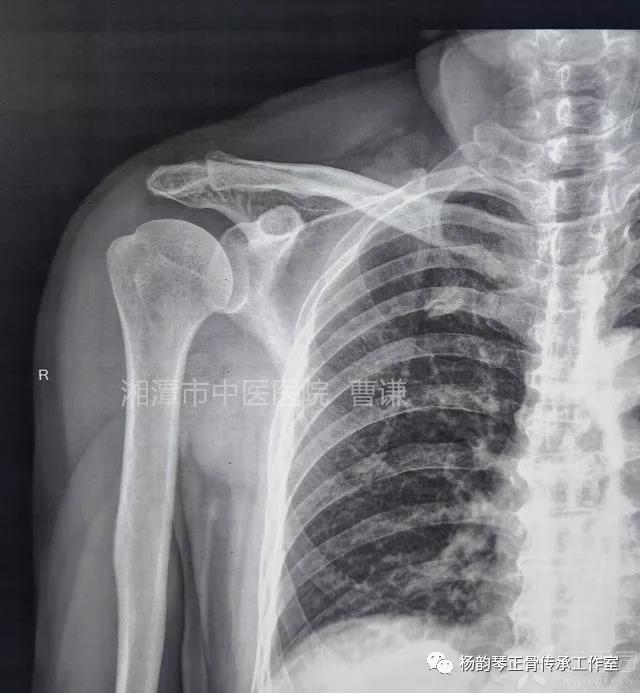

当地接诊医生应该说还是很负责的,同时拍了健侧片对比:

影像科报告,骨科医生光看报告行吗?